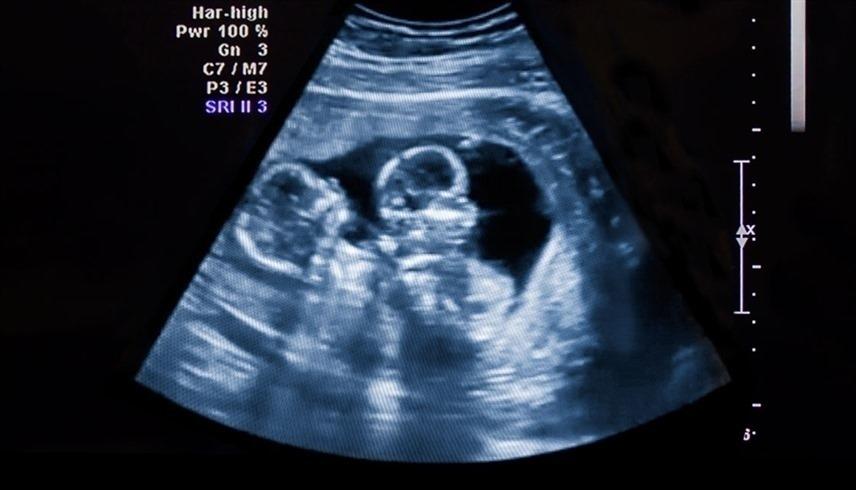

خبرني - يوجد نوعان من حمل التوائم، الأول: التوائم الأخوية غير المتماثلة عندما يتم تخصيب بويضتين بواسطة خلايا منوية مختلفة، وهو النوع الأكثر شيوعاً.

أما النوع الثاني فهو عندما تنقسم البويضة المخصبة إلى قسمين، لتشكل جنينين في الرحم، ويُعرف بالتوائم المتماثلة.